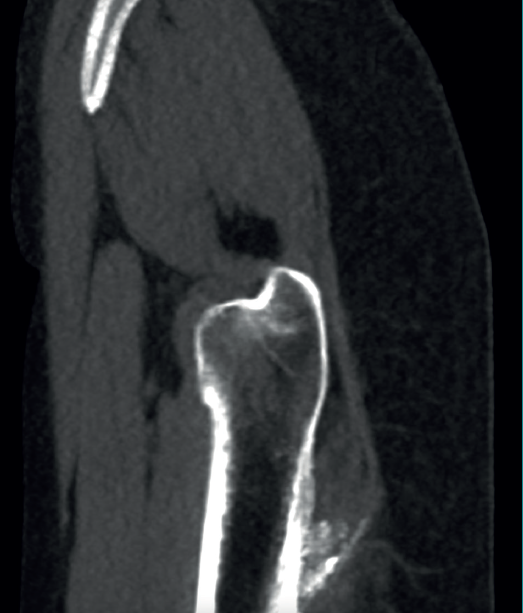

reacae.31181.fs2402007en-figure1.png

The physical examination revealed a limp-free gait and complete joint balance, with no positive signs of femoroacetabular impingement or inguinal pain. Muscle strength was preserved and similar to that of the contralateral side. She experienced intense pain on palpation of the insertion of the gluteus maximus, referred proximally to the ipsilateral buttock. The pain was reproduced on extension against resistance, and prevented sitting for long periods. Plain radiographic and computed tomography (CT) images revealed calcific tendinosis affecting the aponeurotic prolongation of the gluteus maximus in proximity to its insertion in the upper region of the linea aspera of the femur  (Figures 1 and 2) Magnetic resonance imaging (MRI) of the hip showed a labral tear, that proved asymptomatic in the physical examination. In view of the clinical picture of radicular pain, an MRI scan of the lumbar spine and subgluteal space was also performed, ruling out radicular involvement or sciatic neuritis. Her previous treatment over the three years of evolution of the disorder included oral nonsteroidal anti-inflammatory drugs, a specific physiotherapy programme and several ultrasound-guided corticosteroid injections with positive results - though a last session showed no response. Due to the severity and chronicity of the symptoms and their resistance to conservative treatment, surgery was decided to clean and remove the intratendon calcification endoscopically.